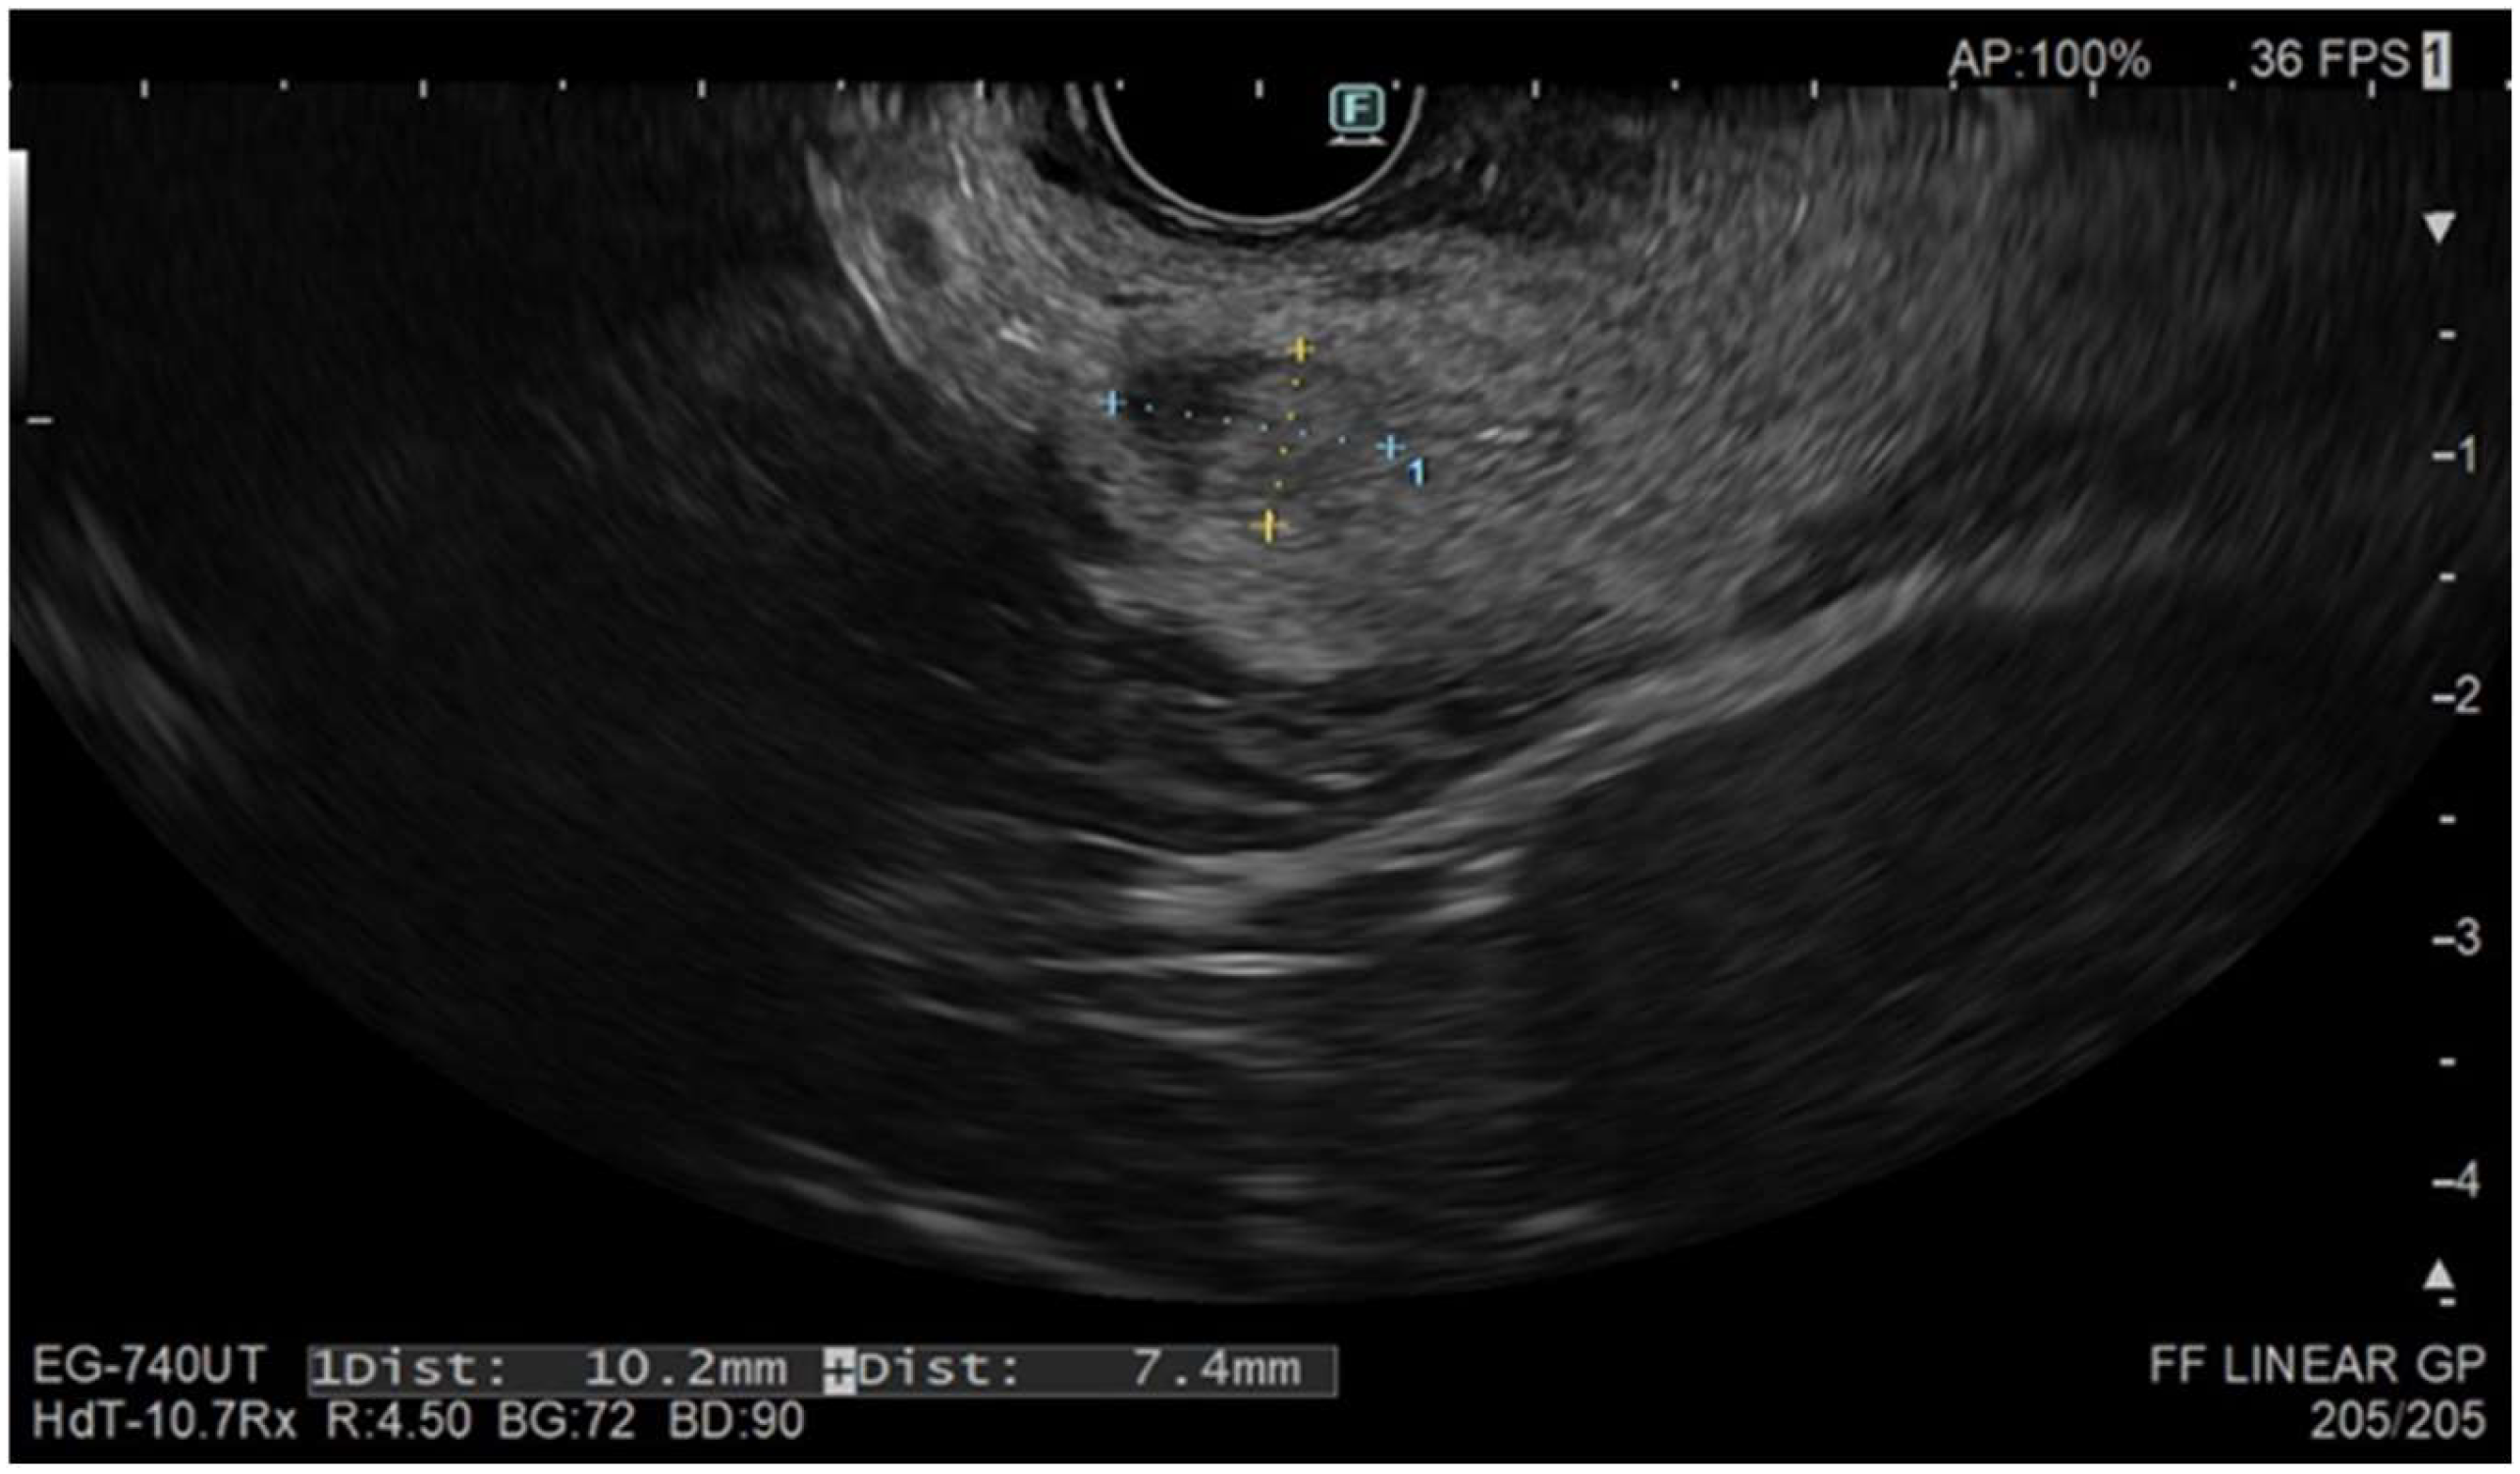

3.3. Role of Contrast Harmonic EUS (CH-EUS) and Follow-Up

- Choi, J.-H.; Seo, D.-W.; Song, T.J.; Park, D.H.; Lee, S.S.; Lee, S.K.; Kim, M.-H. Utility of Contrast-Enhanced Harmonic Endoscopic Ultrasound for the Guidance and Monitoring of Endoscopic Radiofrequency Ablation. Gut Liver 2020, 14, 826–832. [Google Scholar] [CrossRef]